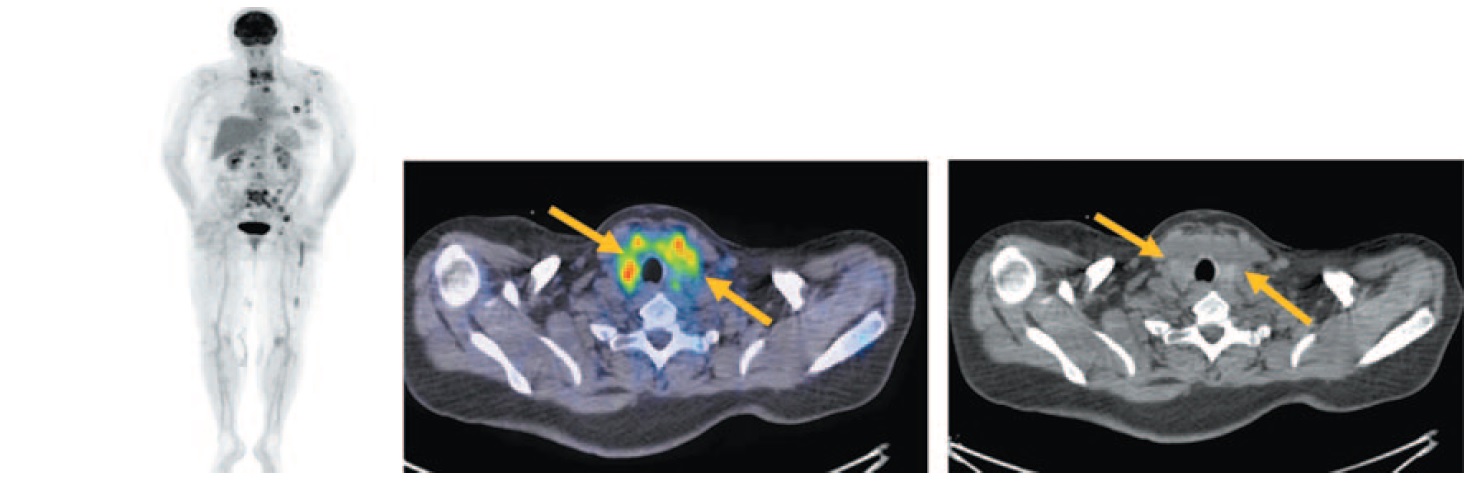

Яичники кистозно измененные с двух сторон, больше справа, размером до 86×134 мм, с перегородками, с диффузной фиксацией 18-ФДГ, SUVmax 5,86.

В костях скелета определяются множественные очаги остеобластической перестройки, с повышенной фиксацией РФП (рис. 11).

Рис. 11. Больная К., 55 лет. На сагиттальных ПЭТ/КТ проекциях в костях скелета определяются множественные очаги повышенной фиксации РФП на фоне остеобластической перестройки костной ткани, SUVmax 4,86.

Fig. 11. A 55-year-old woman. Sagittal PET/CT images show that in the bones of the skeleton are defined multiple focal increased RFP uptake against the background of osteoblastic bone remodeling, SUVmax 4.86.

Заключение: ПЭТ/КТ данные образования левой молочной железы с повышенной метаболической активностью специфического характера. Вторичное поражение щитовидной железы, шейных и аксиллярных лимфоузлов слева, яичников, костей скелета и легких.